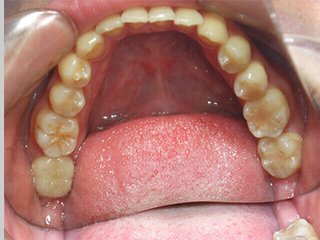

どこを治したかわかりますか?正解は、、、、、、、こうなってました。金属の詰め物、被せ物を取り、中の虫歯や金属片をきれいにし、形を整えたところです(写真は右上だけですが左上も同じようにします)。患者様が他院にて歯科治療を受け、健康保険適用の金属にて治療を終えてからもともとあったアトピー性皮膚炎が悪化し、調べたところ歯科金属アレルギーであったことが判明。当院にご相談に来られました。